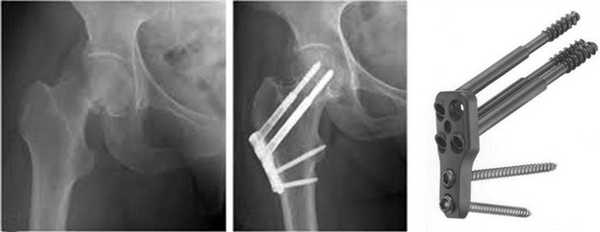

а. рентгенограмма тазобедренного сустава с переломом шейки бедра, б. рентгенограммы после остеосинтеза винтами.

г. перелом шейки на рентгенограмме, д. схематическое изображение остеосинтеза шейки винтами.